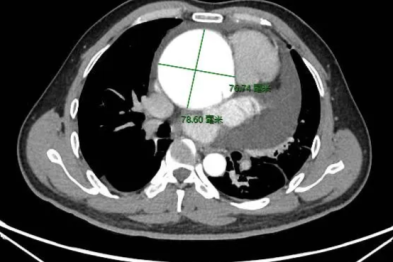

【高尚病例】巨大硬化性肺细胞瘤 1 例